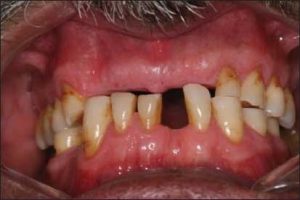

Following diagnostic cast surveying and treatment planning, tooth extractions should be carried out early enough to allow adequate healing. However, each tooth should be evaluated based on its location and potential contribution to the success of the treatment. Teeth that are strategically important and that will support the success of the prosthesis should be retained, while those with a questionable prognosis or that may complicate treatment planning should be extracted (Figure 10-1).